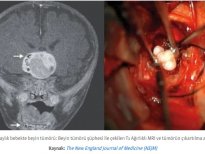

Diş yapısı en dıştan içe doğru mine (kök kısmında sement), dentin, pulpa olarak sıralayabiliriz. Mine, sement ve dentin hidroksiapatit kristalleri dediğimiz kalsifiye yapıdan oluşur ve büyük ölçüde kemiğe benzer. Hidroksiapatit kristalleri dişlere sertliğini verir ve dişlerin molekül yapısında eser miktarda su bulunduğundan dolayı oldukça serttir ve böylece çok büyük çiğneme kuvvetlerine dayanabilirler. Mine, vücuttaki en sert maddedir; öyle ki kemikten bile daha serttir. Bu kadar yoğun kalsifiye yapıların yumuşak dokuda gelişmeleri oldukça zor ve nadir olmasına rağmen çarpıcı örnekleri vardır.